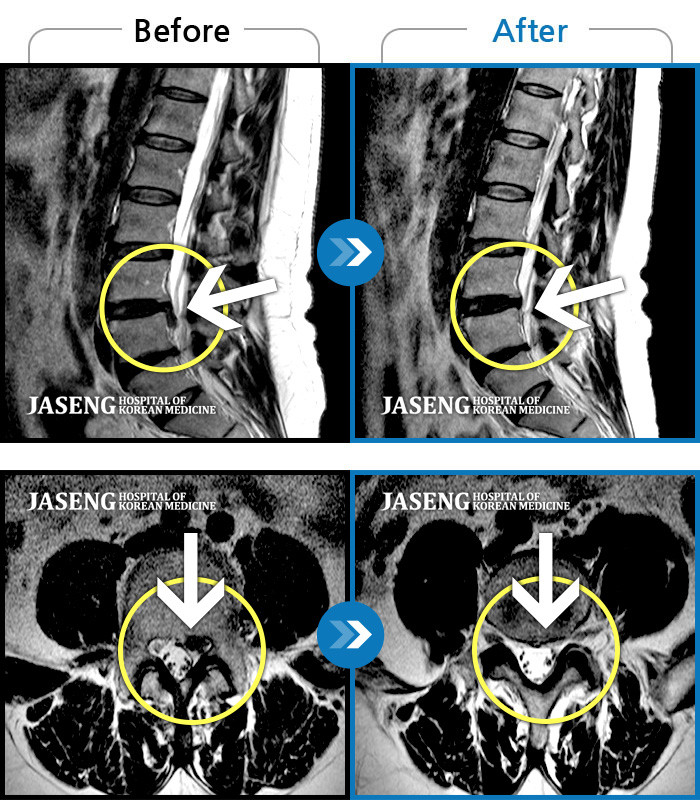

Before

After

환자에게 사전 동의를 받아 동일 조건에서 촬영되었습니다.

개인에 따라 치료 후 부작용이 발생할 수 있으니 의료진과 상담 후 치료를 진행하시기 바랍니다.

교통사고로 인해 기존의 퇴행성 디스크가 파열되어 극심한 경추의 통증과 손의 힘 빠짐, 손가락의 저림 증상을 호소하였음